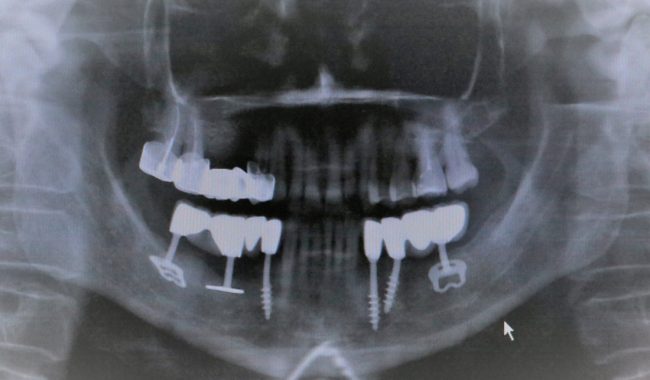

Итак, имплантаты установлены:

После операции и небольшой коррекции я вернул Ростиславу его съемный протез. Шеф назначил послеоперационную терапию. Осталось подождать интеграции, ориентировочно 4 месяца.